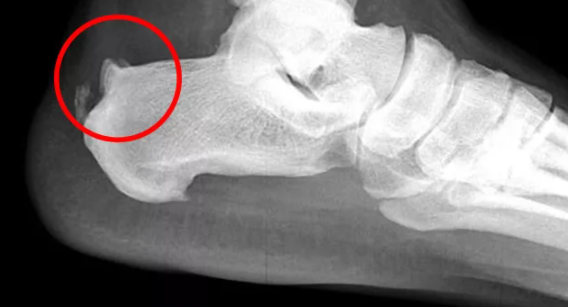

Немного о пяточной шпоре. Вкратце. Как видим на рисунках ниже, его правильное формирование зависит от состояния связок. Связки крепятся не к кости, а к надкостнице (периост).

Если связка по тем или иным причинам теряет эластичность, стянута, это может привести к отслоению (оттягиванию) участка надкостницы (периоста). Которая крепится с помощью коллагеновых пучков. В образовавшейся полости возникают воспаления, может возникать периостит (воспаление тканей надкостницы), но не об это речь.

В нашем случае, в области пяточной кости формируется кальцифицированный вырост – остеофит. При плоскостопии особенно часто натянутость связки провоцирует образование "пяточной шпоры".